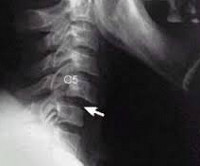

Основным методом диагностики подвывиха шейных позвонков является рентгенография позвоночника. Используются как стандартные проекции (боковая и прямая), так и дополнительные: косые снимки, рентгенограммы через рот, а также снимки в положении сгибания и разгибания шеи. Выбор дополнительных проекций зависит от предполагаемого уровня повреждения. Также могут быть назначены КТ и МРТ.

На КТ позвоночника можно увидеть уменьшение высоты диска и смещение суставных поверхностей. При подвывихе С1 наблюдается асимметрия между атлантом и зубом. МРТ позволяет уточнить состояние мягких тканей. Пациентам с подозрением на подвывих позвонков рекомендуется консультация невролога для выявления возможных неврологических нарушений. При хронических подвывихах и подозрении на ухудшение кровоснабжения головного мозга показана реоэнцефалография.

• Рентгенография — показывает степень смещения позвонка;

1. Спондилография — визуализирует состояние позвонков, суставов и дисков. При необходимости назначаются другие виды рентгенографии.

2. Косые рентгенограммы — необходимы для четкой визуализации отростков суставов и межпозвоночных отверстий. Процедура выполняется при наклоне на 45 градусов.

3. Рентгенография через рот — позволяет визуализировать только первые два позвонка и помогает выявить ротационный подвывих атланта.